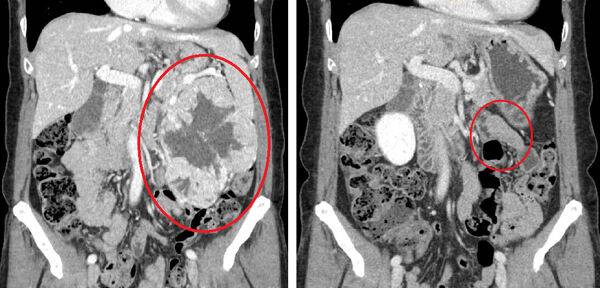

순천향대 부천병원은 비뇨의학과 이상욱 교수가 최근 로봇수술로 21cm에 달하는 '초거대 신장암'을 제거하는 데 성공했다고 29일 밝혔다.

지금까지 로봇수술로 제거 가능한 신장암의 크기는 최대 15cm로 알려졌지만, 최근 이상욱 교수는 환자 홍 씨(여·59세)의 왼쪽 신장에 생긴 21cm 종양을 로봇수술로 완전히 제거하는 데 성공했다.

신장은 수술 시 출혈 위험이 큰 장기이다. 심장이 내보내는 혈액 25%가 신장을 지나고, 혈관이 복잡하게 얽혀있기 때문이다. 로봇을 이용한 신장암 수술은 기존의 개복 또는 복강경 수술보다 수술 시 출혈과 합병증을 최소화할 수 있으며, 수술 후 통증이 적어 진통제 사용량을 대폭 줄일 수 있다.

이상욱 교수는 ”로봇수술은 최대 15배까지 확대되는 입체적인 시야와 360도 회전하는 로봇팔로 더 정교한 수술이 가능해, 수술 시 다른 장기 손상을 최소화할 수 있으며 회복이 빠른 것이 큰 장점이다. 육안으로 보이는 상처도 0.8cm 정도로 작아 수술 흉터에 민감한 여성들의 만족도가 높다. 이번 ‘로봇수술을 통한 초거대 신장암 치료 성공사례’가 기존 수술법을 망설이는 환자들에게 좋은 치료법이 될 것“이라고 말했다.